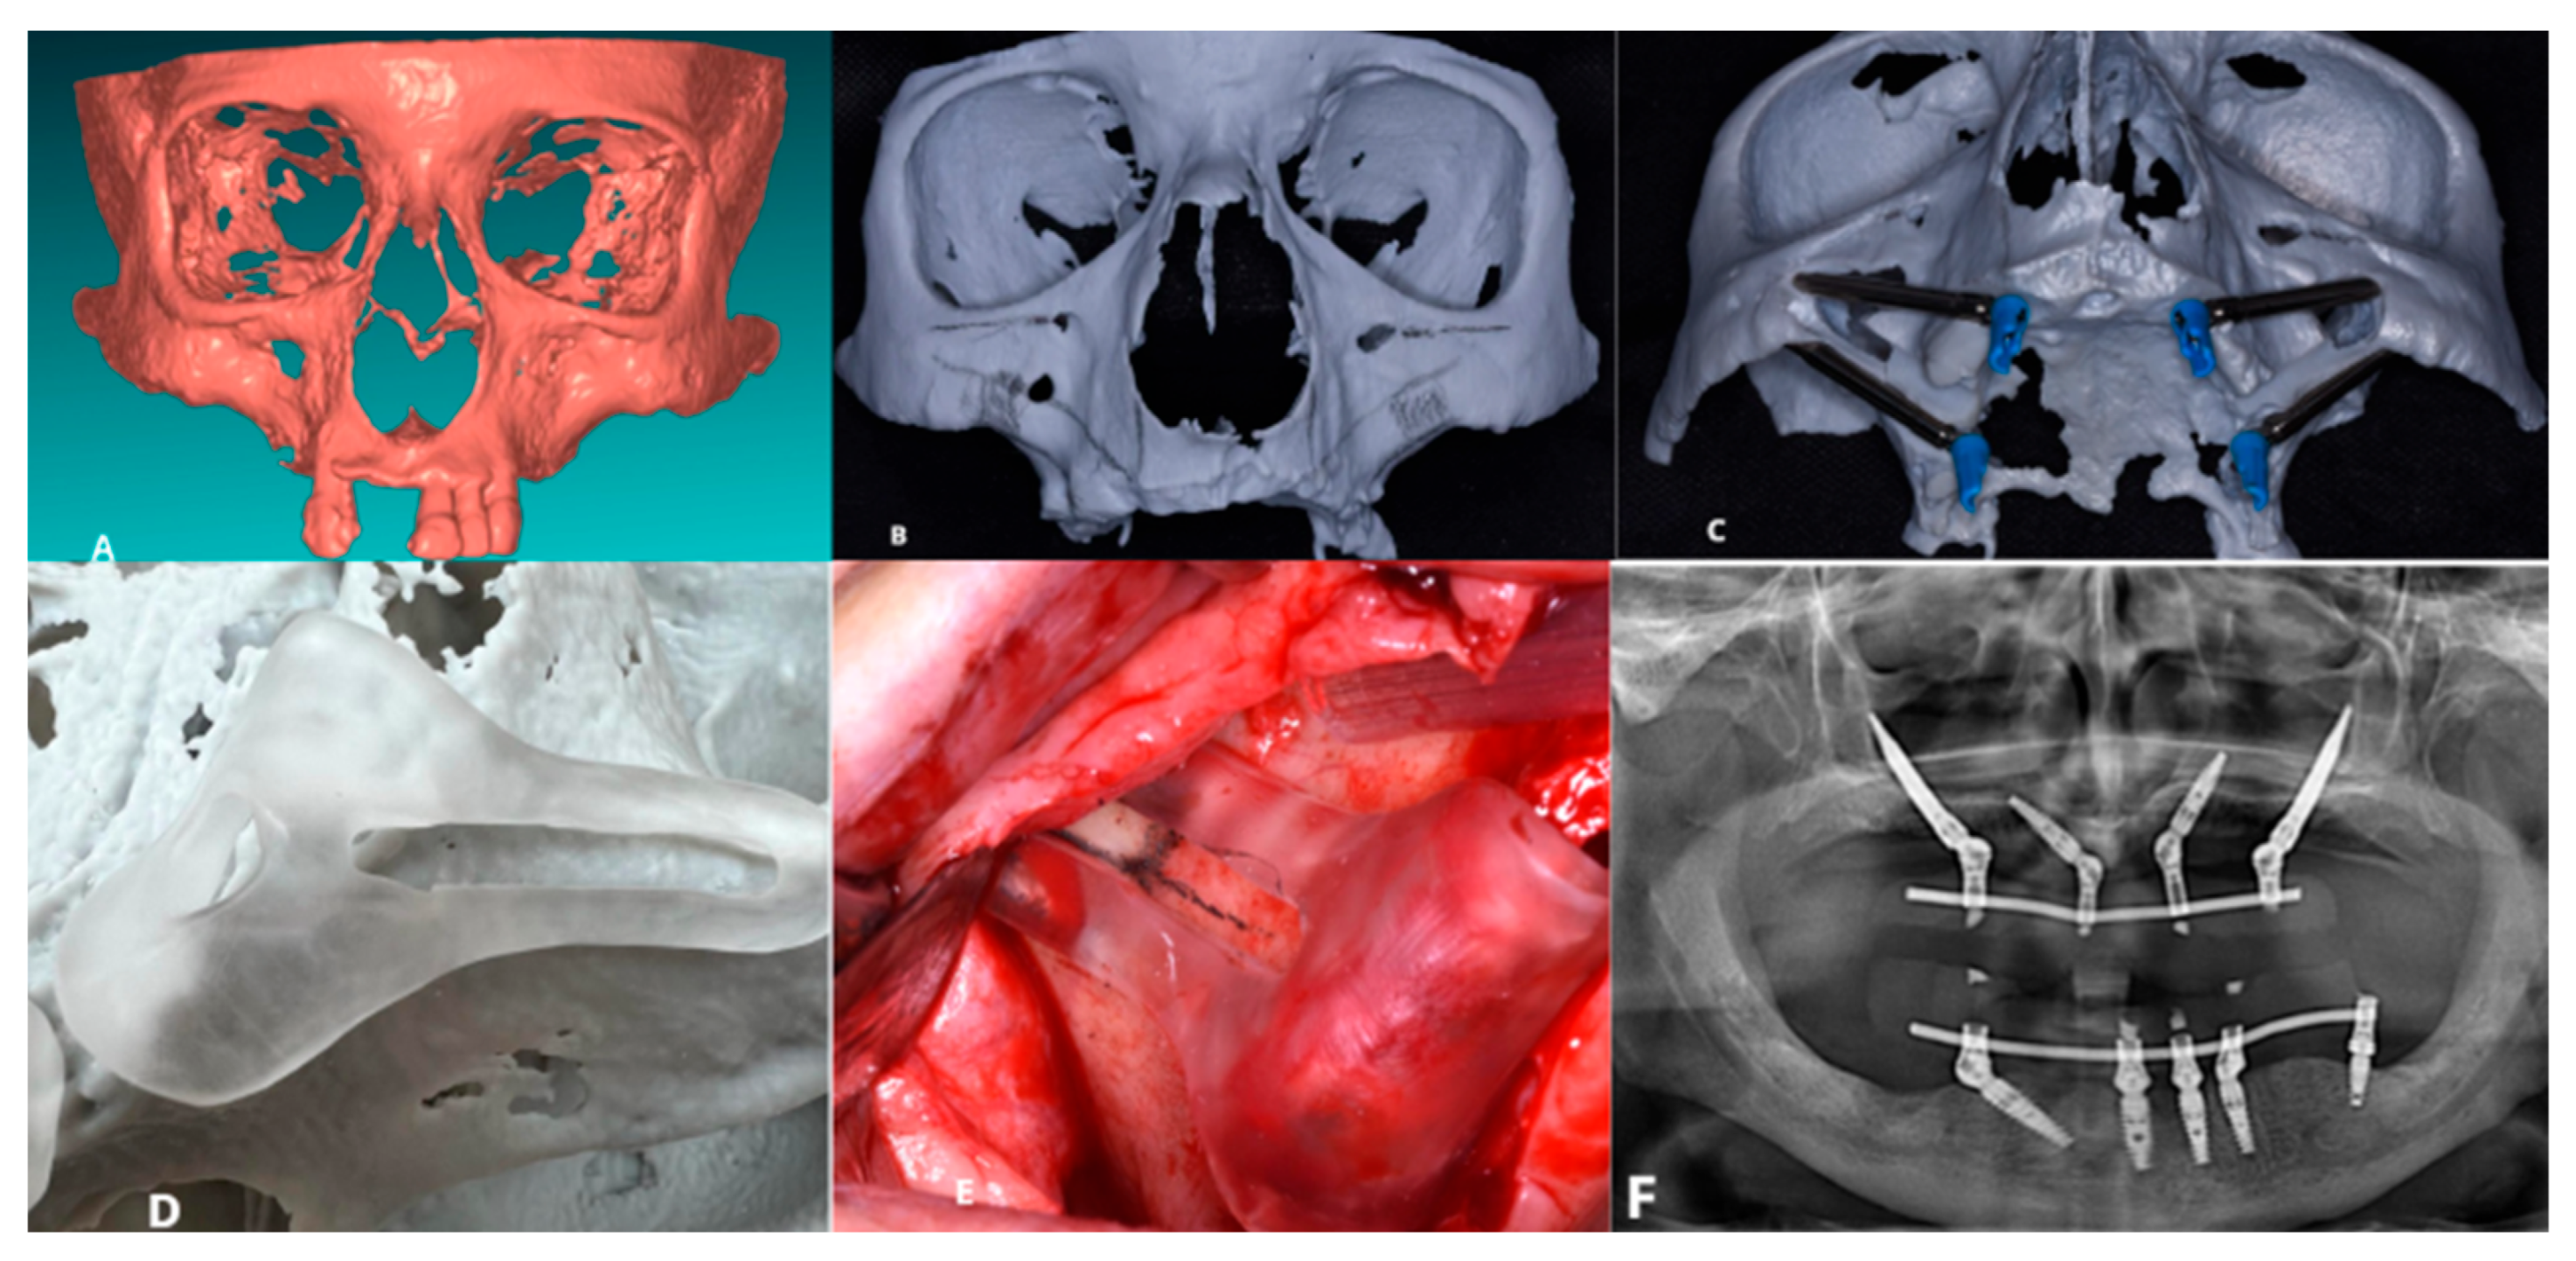

2.4. Case 2